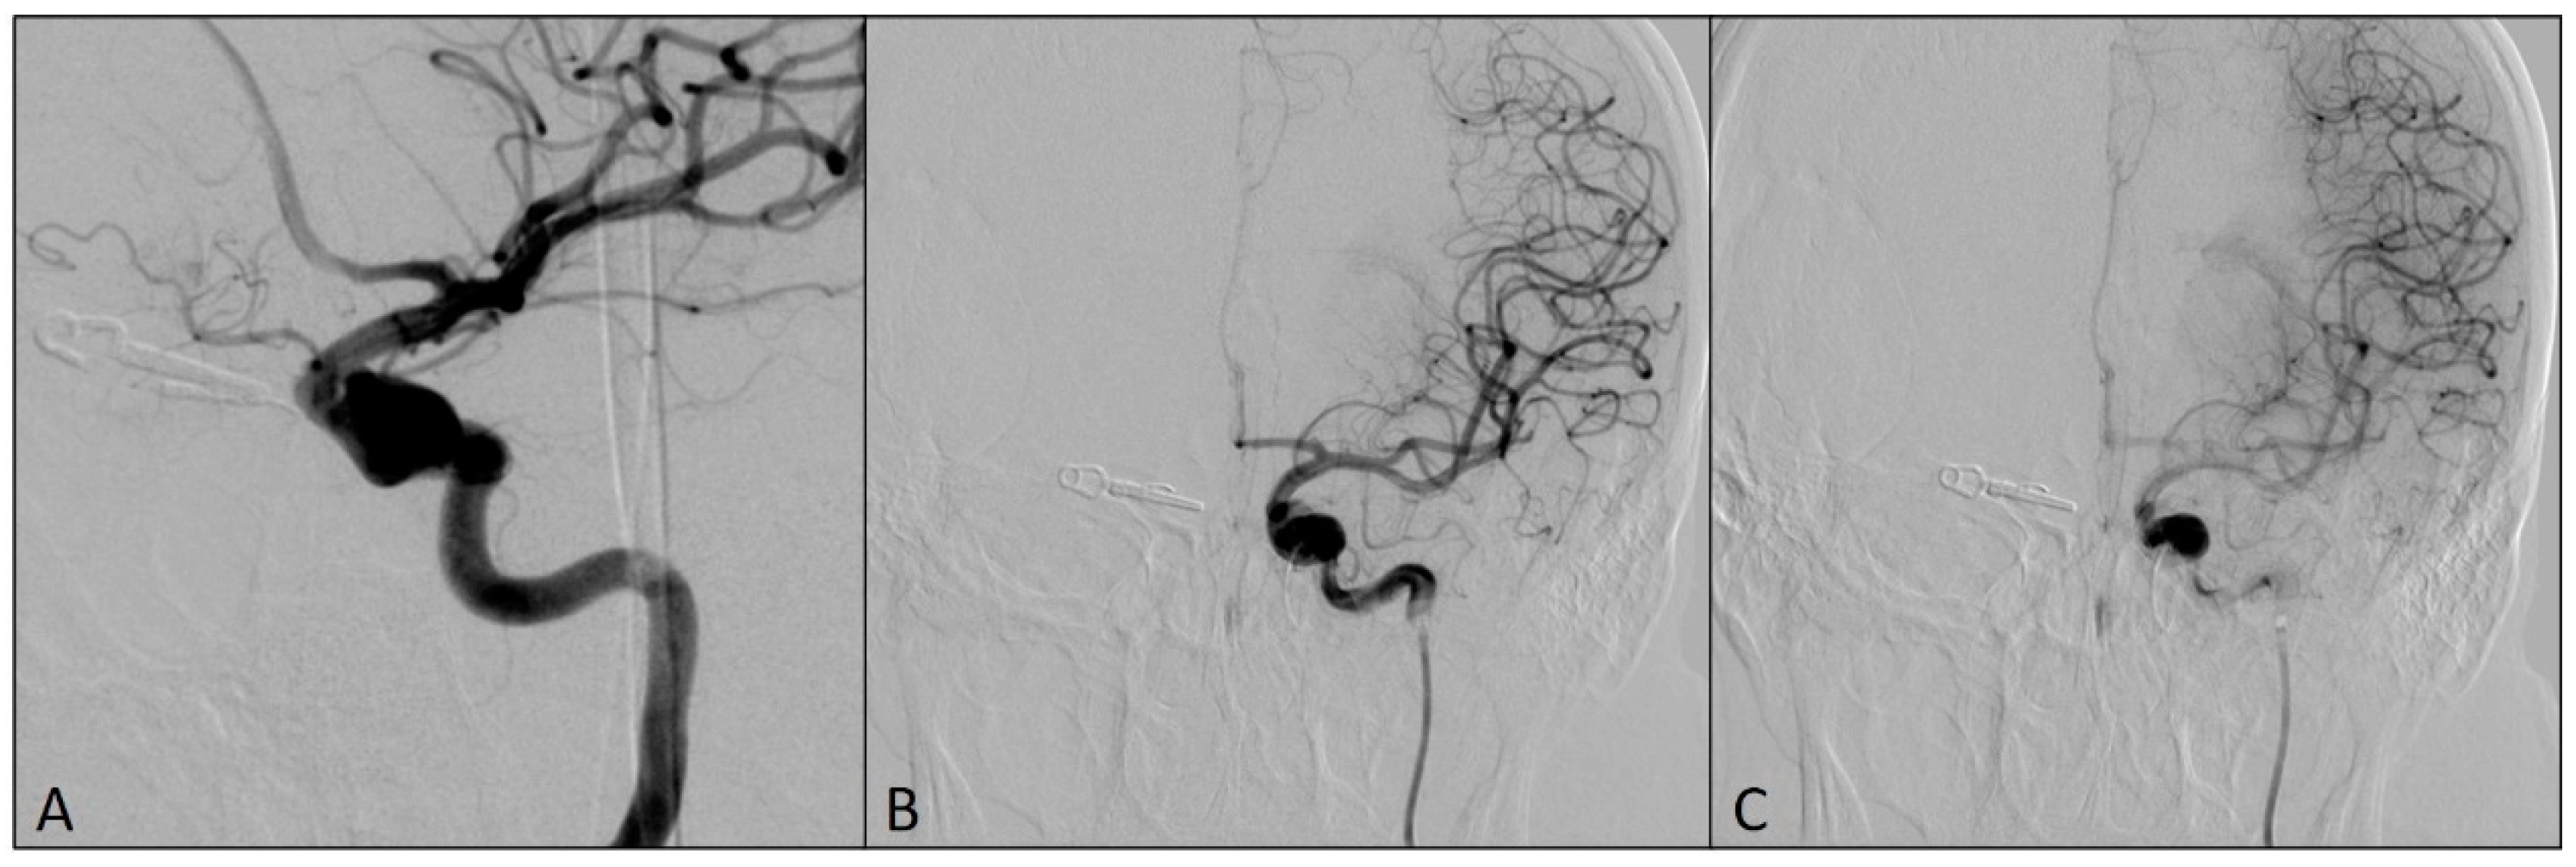

2. Case Report